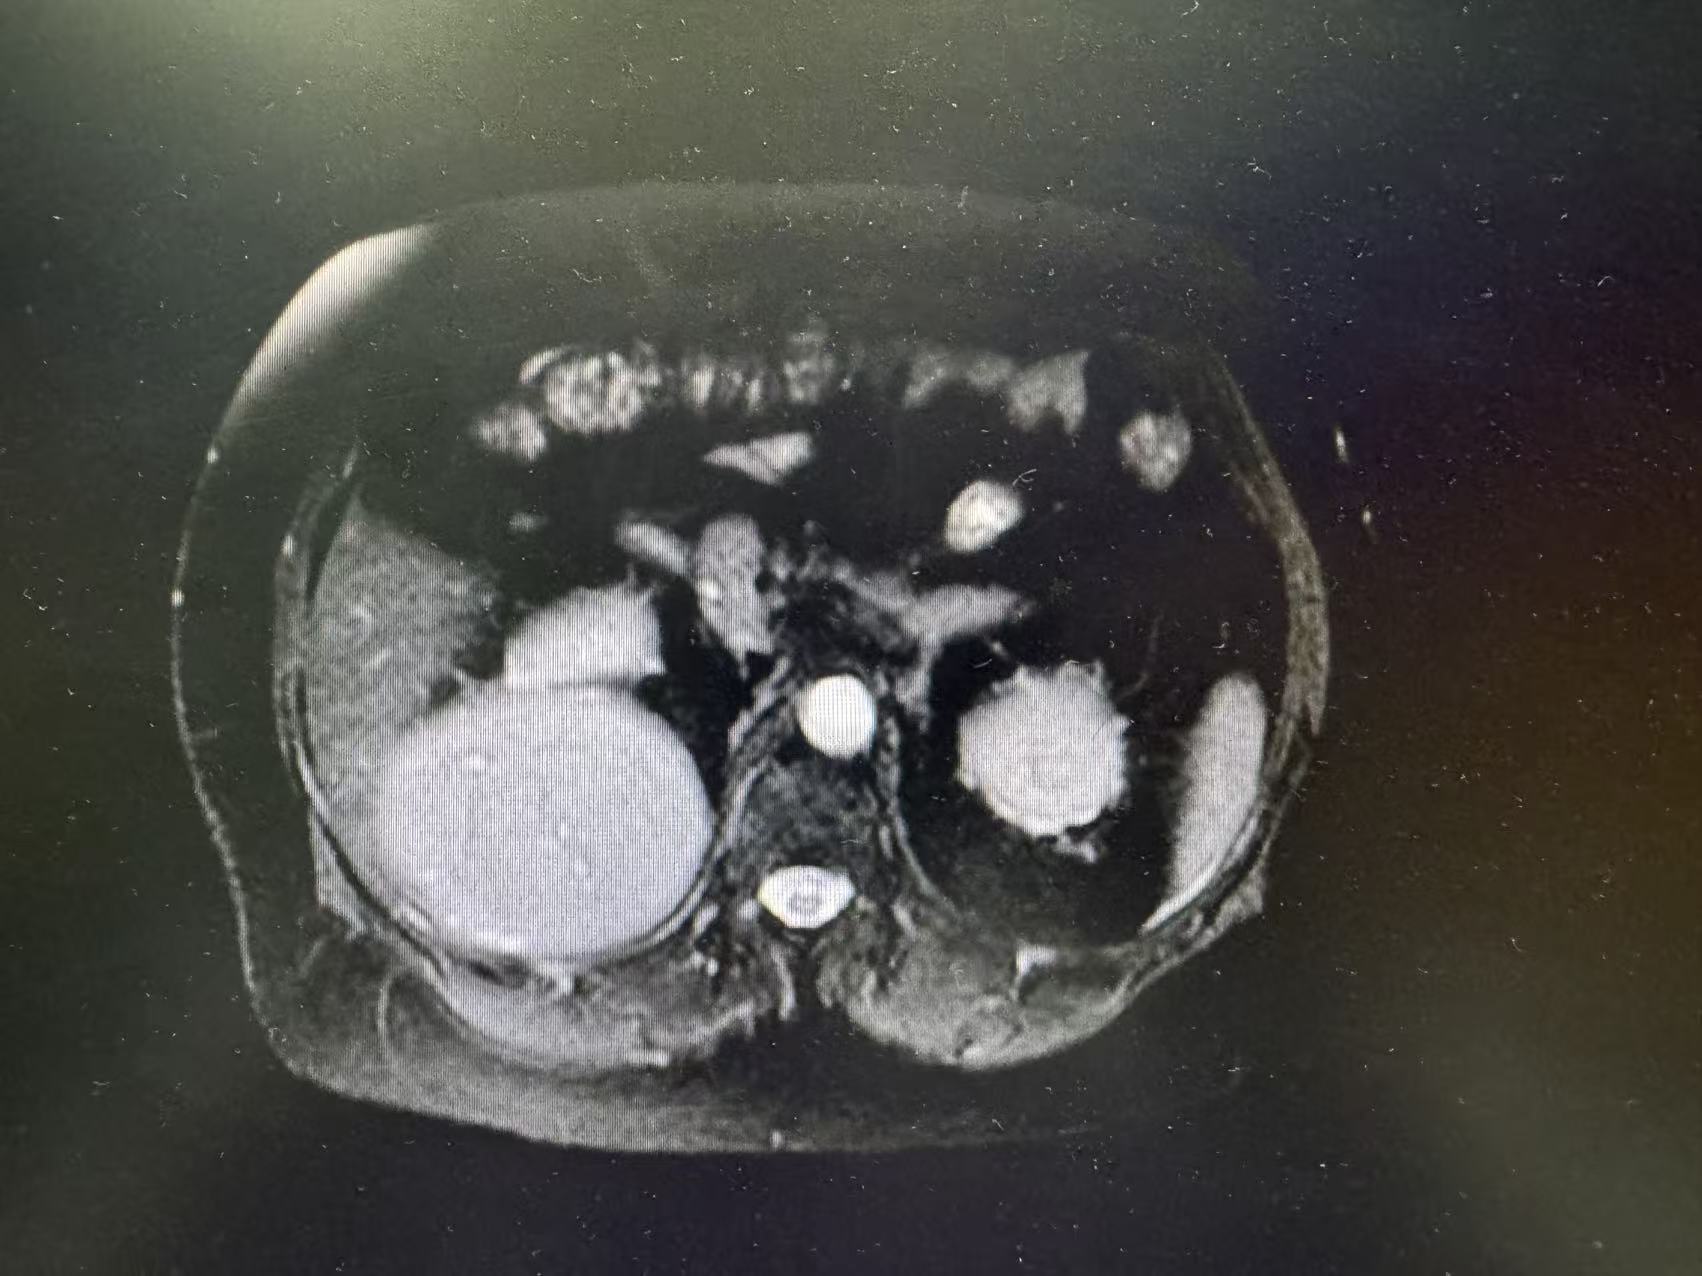

术前肿瘤影像数据

入院后,张玉宝教授立即带领团队对患者病情进行全面细致评估,启动多学科会诊(MDT),联合影像中心、麻醉科、重症医学科等专家,精准研判肿瘤侵犯范围、血管受累程度及脏器功能状态。结合二次开腹手术的特殊性,团队反复优化手术入路与切除策略,充分预判术中可能出现的致命风险,制定周密的个体化手术方案与应急预案,为手术安全筑牢坚实基础。